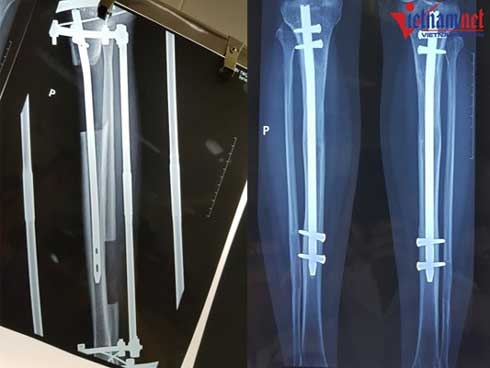

Tuy nhiên từ năm 2010 đến nay, BV 108 cải tiến kĩ thuật, đặt chiếc đinh dài trong ống tủy xương trước khi cắt, giảm số đinh xuyên qua xương chỉ còn 4 đinh và thời gian nằm tại giường chỉ còn 2-3 tháng. Nhờ có đinh cố định, xương khi liền sẽ không bị chệch.

Để đặt đinh, bác sĩ sẽ rạch da dài khoảng 1,5-2 cm dọc mặt trước gân bánh chè, sau đó khoan ống tủy và đóng một đinh dài 24-28cm vào ống tủy xương chày.

Một chiếc đinh dài được đặt trong lòng ống tủy (trái) và bác sĩ sẽ bắt chốt 2 đầu đinh lại sau khi đạt chiều cao mong muốn

Khi đạt đến chiều cao mong muốn, bác sĩ sẽ bắt chốt 2 đinh lại với nhau và tháo bỏ khung ngoài. Bệnh nhân sẽ được bó bột, sau đó bắt đầu tập đi dưới sự trợ giúp của khung hoặc nạng.